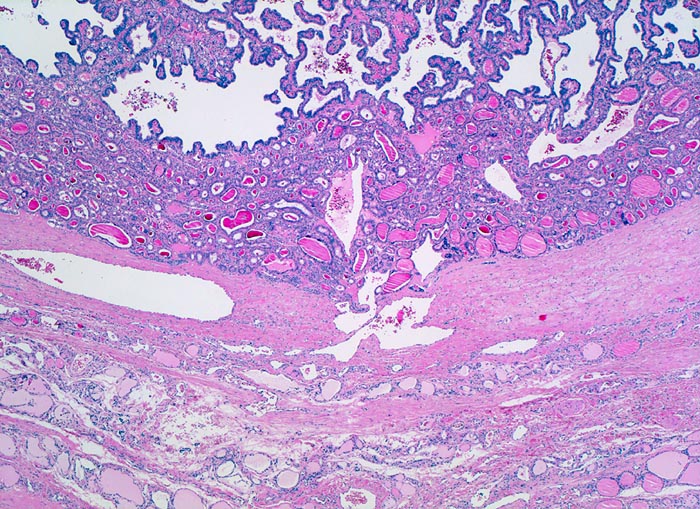

PathoPic ID 4735 - papilläres Schilddrüsenkarzinom

papilläres Schilddrüsenkarzinom

maligner Tumor

Schilddrüse

Endokrinium

Bindegewebige

Kapsel zwischen Karzinom und

atrophem Parenchym. Das Karzinom bildet

Follikel und

papilläre Strukturen.

In der Feinnadelpunktion eines 2cm grossen kalten Knotens werden Karzinomzellen nachgewiesen vereinbar mit einem papillären Schilddrüsenkarzinom.

Nur etwa 10% der papillären Karzinome sind vollständig bekapselt. Die bekapselten Tumoren haben eine bessere Prognose.

Histologie

25